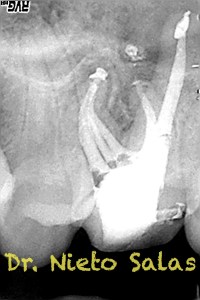

Os presento unos casos de varios molares superiores, con tres conductos mesiovestibulares con un foramen o con dos.

Una vez que tenemos medidas, obturamos los conductos:

No es habitual en nuestra práctica casos como estos, pero os pongo algunos más: